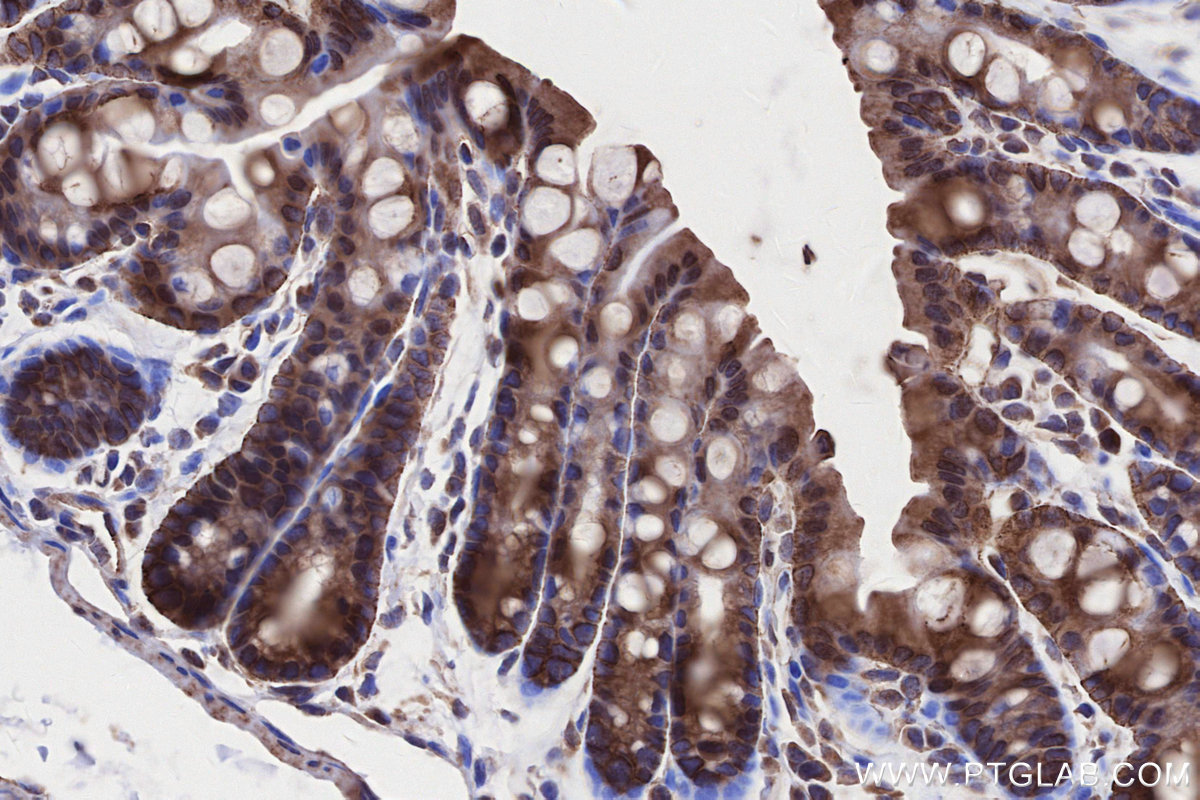

Validation Data Gallery